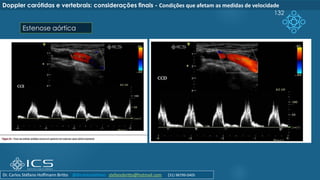

Condições que afetam as medidas de velocidade

 Algumas condições afetam as medidas da análise espectral.

 Elas podem estar localizadas na bifurcação carotídea, distal ou proximal a ela ou ainda na

carótida contralateral.

 Dentre as condições proximais à bifurcação ressaltamos as valvopatias aórticas (estenose

ou insuficiência), estenoses de origem aterosclerótica ou arterites com envolvimento do

arco aórtico, ramos e carótida comum. Disfunção sistólica do ventrículo esquerdo de grau

importante, as arritmias cardíacas, taquicardias e bradicardias

 Na presença de estenose aórtica importante há turbulência do fluxo, as velocidades

podem estar reduzidas e, mesmo na presença de estenose carotídea significativa ao

modo B, as velocidades absolutas podem não atingir os valores de velocidade

preconizados para sua quantificação.

 Podemos citar ainda: Disfunção sistólica do ventrículo esquerdo de grau importante, as

arritmias cardíacas, taquicardias e bradicardias

132

Doppler carótidas e vertebrais: considerações finais - Condições que afetam as medidas de velocidade

Estenose aórtica

Dr. Carlos Stéfano Hoffmann Britto @drcarlosstefano stefanobritto@hotmail.com (31) 98799-0405